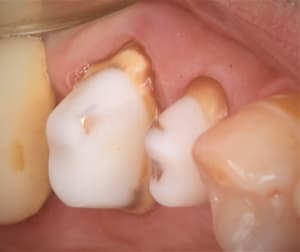

5A1ED2F3-46A0-45CF-8A09-ED06780C966D_dy9y3z.jpg

B4FABAC8-3F0A-44D1-A45E-D18E22A95ACB_zudxel.jpg